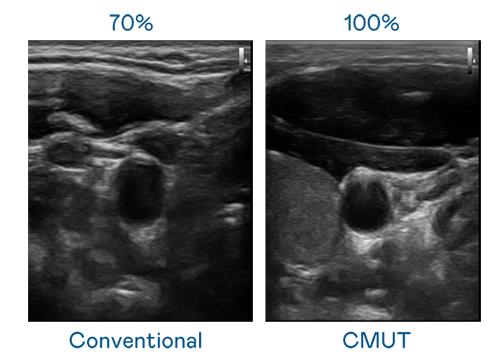

申博太陽城運用 TFT 陣列 (Array) 制程延伸尖端感測技術(shù) ,開發(fā)出多種感測元件的產(chǎn)品。高解析度、品質(zhì)穩(wěn)定且可量產(chǎn)的 CMUT 元件 ,可制作高解析度超音波探頭 、貼片型探頭 ,對病患實施精準(zhǔn)檢測與長時間生理監(jiān)測 。為滿足 X光設(shè)備輕量化、可移動 ,甚至需針對待測物進行外觀客制化的新需求 ,申博太陽城結(jié)合非晶矽 (a-Si) 制程與新的封裝技術(shù) ,實現(xiàn)可撓曲、具優(yōu)異 TFT 遷移率 (mobility) 的柔性 X光感測器。目前也已提供完整玻璃和曲面型 X光感測器檢測解決方案 。